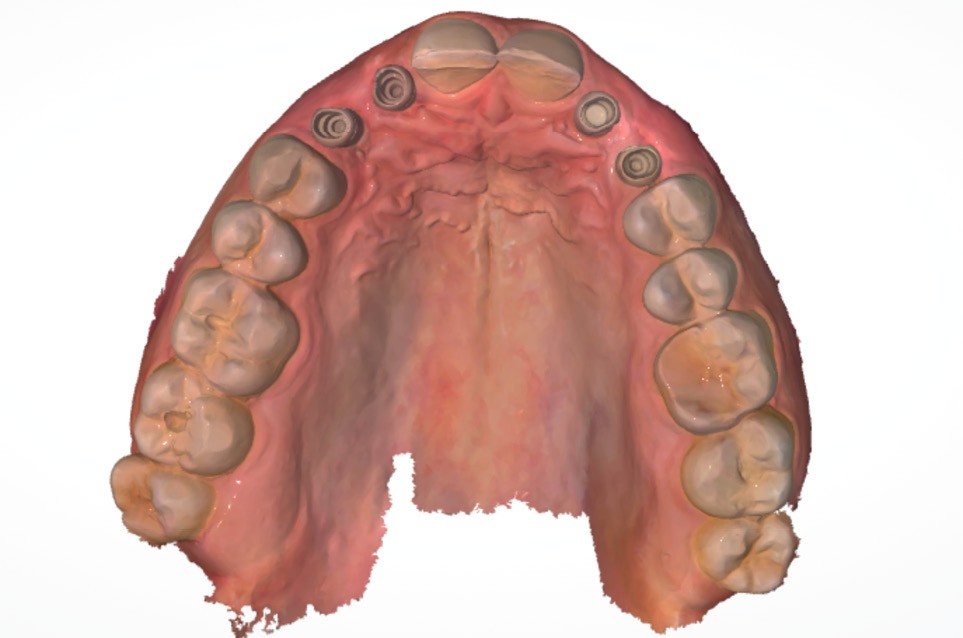

Un homme de 38 ans se présente en consultation d’implantologie pour le remplacement de ses 4 dents lactéales 52 53 62 63. Il ne présente pas d’antécédents médicaux, chirurgicaux, pas d’allergie, est non-fumeur. L’analyse clinique, radiologique et préprothétique fait apparaître (fig. 1) :

- les agénésies de 12 13 22 23 46 ;

- des usures marquées des bords libres des dents lactéales ;

- une égression compensatrice de certaines dents antérieures mandibulaires ;

- un parodonte sain et épais.

- réalisation de l’empreinte optique pour enregistrer la position implantaire (Scanbody IOFlO) (fig. 7) ;